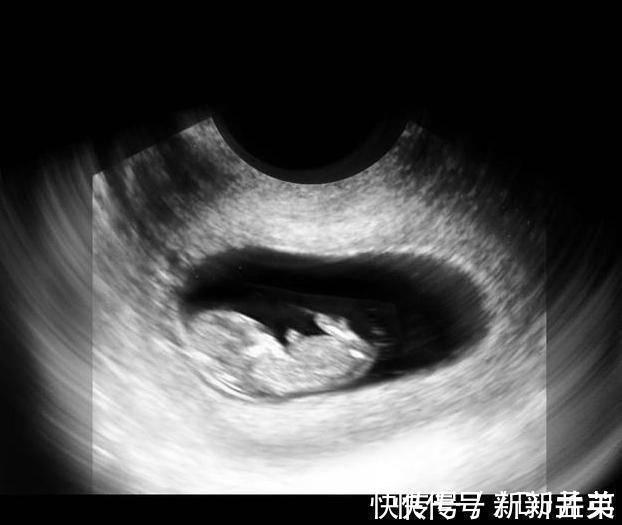

上图可见子宫中的囊状结构,胎儿由两层的组织构成胚胎,所有的器官和组织都是有这些组织发育而成,胚胎羊膜囊的空腔中,开始有羊水积聚,为将来包裹和保护胎儿做准备。